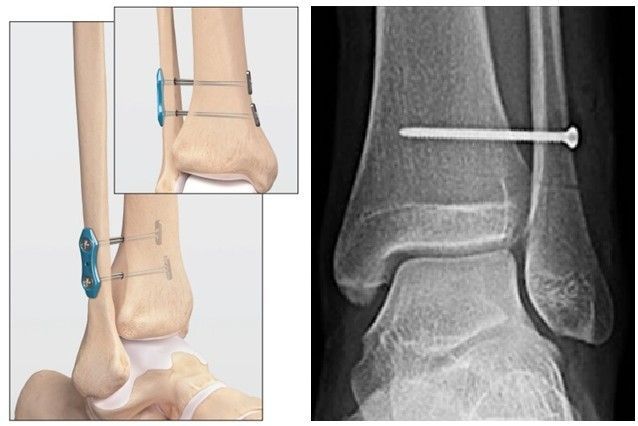

Parafuso ou Tightrope? Qual a melhor opção e preciso remover o material depois de um tempo?

A escolha entre parafuso e Tightrope (ou "sutura em botão") é um dos pontos mais importantes e discutidos no tratamento cirúrgico da lesão da sindesmose. Ambas as técnicas visam estabilizar a pinça do tornozelo, mas funcionam de maneiras diferentes e apresentam vantagens e desvantagens.

Parafuso (Fixação com Parafuso Transindesmótico):

Como funciona:

- Um ou mais parafusos metálicos são inseridos através da fíbula, da sindesmose e da tíbia, fixando os dois ossos firmemente.

Vantagens:

- Técnica tradicional, resultados comprovados em estabilidade inicial.

Desvantagens:

- Rigidez: O parafuso cria uma fixação rígida, o que pode limitar a mobilidade natural da sindesmose.

- Necessidade de Remoção: Geralmente, o parafuso precisa ser removido em uma segunda cirurgia (entre 6 a 12 semanas após a primeira), especialmente em atletas ou pessoas ativas, para permitir o movimento normal da sindesmose e evitar a quebra do parafuso por fadiga do material.

- Complicações: Risco de quebra do parafuso antes da cicatrização, irritação dos tecidos moles.

Tightrope (Fixação com Sutura em Botão ou Sistema de Fita):

- É um sistema dinâmico que utiliza uma sutura de alta resistência (fita) com dois "botões" metálicos em cada extremidade. A fita passa pelos ossos da fíbula e tíbia, e os botões fixam a fita nas superfícies ósseas, mantendo os ossos unidos.

- Fixação Dinâmica: Permite um micro-movimento natural entre a tíbia e a fíbula, o que é crucial para a biomecânica normal do tornozelo. Isso pode reduzir o risco de artrose precoce.

- Não Necessita Remoção: Na maioria dos casos, o Tightrope não precisa ser removido, eliminando a necessidade de uma segunda cirurgia.

- Recuperação Mais Rápida: Pacientes podem iniciar a mobilização e o apoio de peso mais precocemente em comparação com a fixação rígida.

- Custo um pouco mais elevado, técnica que exige treinamento específico do cirurgião.

Qual a melhor opção?

A escolha entre parafuso e Tightrope é individualizada e deve ser discutida com seu cirurgião. Dr. Felipe Serzedello avaliará seu caso, nível de atividade e as características da lesão para recomendar a melhor abordagem. Frequentemente, a técnica com Tightrope é preferida devido aos seus benefícios dinâmicos e à eliminação da necessidade de uma segunda cirurgia, especialmente para pacientes mais jovens e ativos.